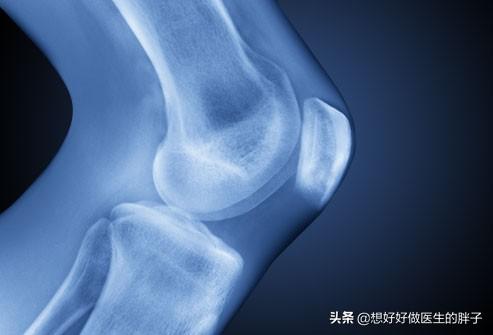

●私は関節に問題を抱えている。..この症状は高齢者に多く、60歳以上になると変形性関節症になる可能性が非常に高くなることを知っておく必要がある。63~70歳では27%に変形性膝関節症の画像所見があり、80歳以上では44%に達する。.そのため、変形性関節症を発症し始めた関節では、関節腔内の軟骨がすり減り、患者によっては少量の骨の再浮上も生じているため、過度の食事の後、問題のある関節で長時間歩くと、変形性関節症の変化を悪化させ、関節の痛みにつながる可能性がある。

アドレス45歳以上で、食後の歩行が原因ですでに関節に大きな痛みがある場合は、病院で膝関節のレントゲン検査を受け、関節に問題があるかどうかを判断することをお勧めします。その後、関節の状態に合わせて食後のウォーキングの時間や回数を調整する。。

もし患者が高齢で、すでに60歳以上のレントゲン検査で、関節に明らかな変性があることが判明した場合、食後1時間の歩行は少し多すぎるかもしれないので、時間を30分に調整し、痛みが軽減したか消失したかを観察することをお勧めします。それでも症状が緩和されない場合は、病院に行って系統的な治療を受ける必要があります。

膝の痛みは、膝の傷害の発生を警告するものであり、早期に整形外科クリニックを受診し、レントゲン検査を受けることをお勧めする。この場合、ウォーキングを続けることは絶対にお勧めできません。膝への負担が少ない水泳に切り替えるとよいでしょう。